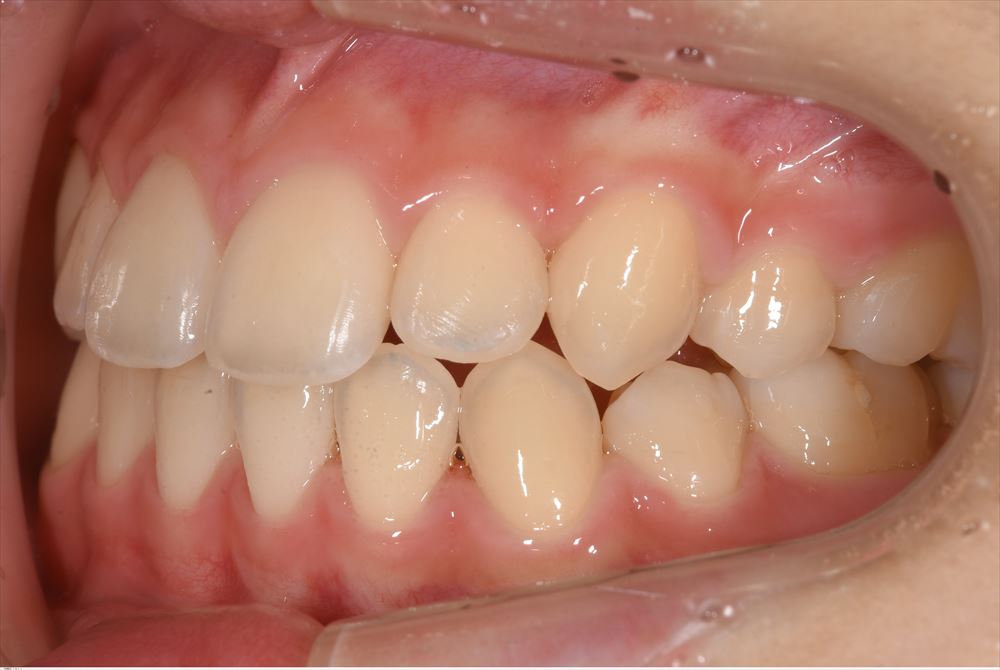

次のケースはハイブリットのセット

これは仮歯。仮歯入れない事はありません。歯茎の為。かみ合わせの為必須。

仮歯を外して